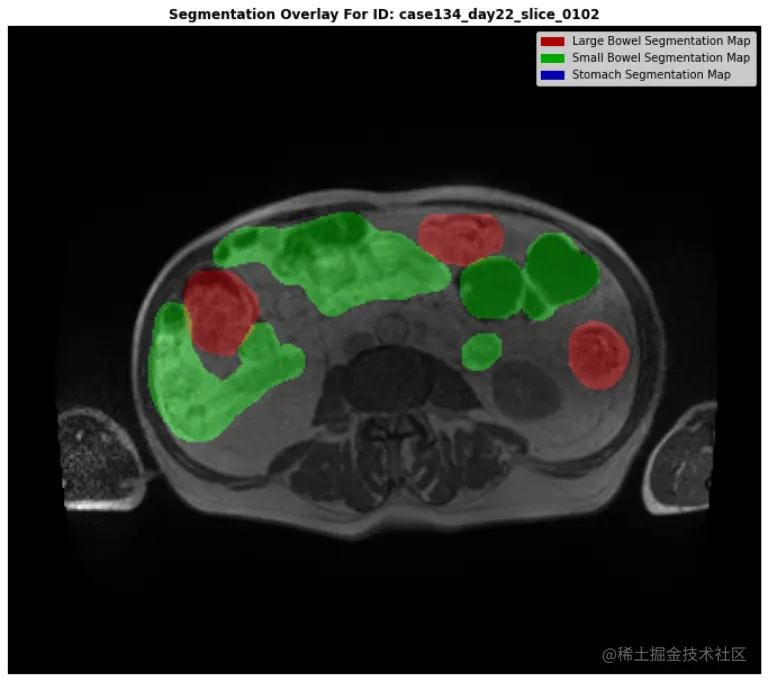

plt.title(f"Segmentation Overlay For ID: {demo_ex.id}", fontweight="bold")

handles = [Rectangle((0,0),1,1, color=_c) for _c in [(0.667,0.0,0.0), (0.0,0.667,0.0), (0.0,0.0,0.667)]]

labels = ["Large Bowel Segmentation Map""Small Bowel Segmentation Map""Stomach Segmentation Map"]

print("\n\n\n... EXAMINE AN EXAMPLE WITH A LARGE AMOUNT OF SEGMENTATION MASK ...\n")

examine_id("case134_day22_slice_0102")